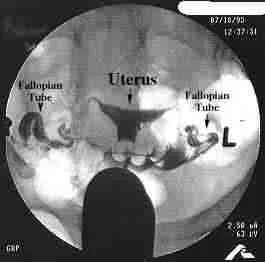

- A-Hysterosalpingography = H.S.G: the main line used for diagnosis by “tubal patency tests”.

The idea: Inject radio-opaque dye in the uterus to pass through the tubes to the peritoneal cavity.

Then the lower abdomen and pelvis are photographed.

Timing of the test: it should be done post-menstrual to minimize chances of interrupting a pregnancy.

B-Laparoscopy with Dye Injection:

- By injection of methylene blue dye through the cx if passed from the fimbrial end = patent tubes.